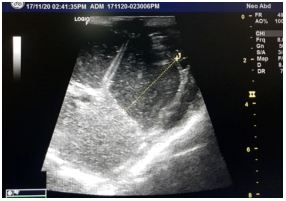

She delivered a male child at 40 weeks of gestation by normal vaginal delivery with no perinatal complications. postnatal ultrasound was done which confirmed antenatal findings of dilated bowel loops of around 10cm in length and 3cm in width, no echogenic material within (Figure 2).

Figure 2: Ultrasound abdomen showing dilated bowel loops without ascites and calcification